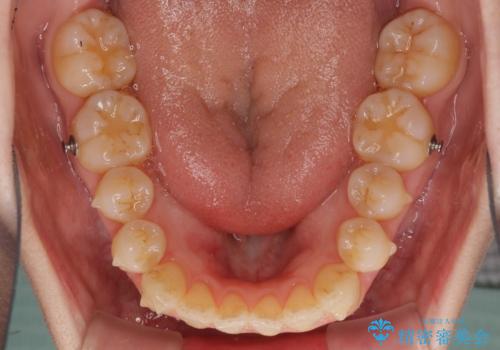

前歯の叢生とオープンバイト インビザラインでの矯正治療

- 前歯の開咬を気にして来院された患者様です。

開咬の治療は、前歯を閉じるように動かすとともに、上下臼歯を圧下(骨内にめり込ませる)させることで進めて行きます。

インビザラインは臼歯の圧下を効果的に行えるため、インビザラインを用いて矯正治療を行うこととしました。

オープンバイトは舌の突出癖により誘発され、治療後も突出癖が残っている容易に後戻りしてしまいます。

治療期間を短縮するためにも、舌突出癖の改善が極めて重要となります。